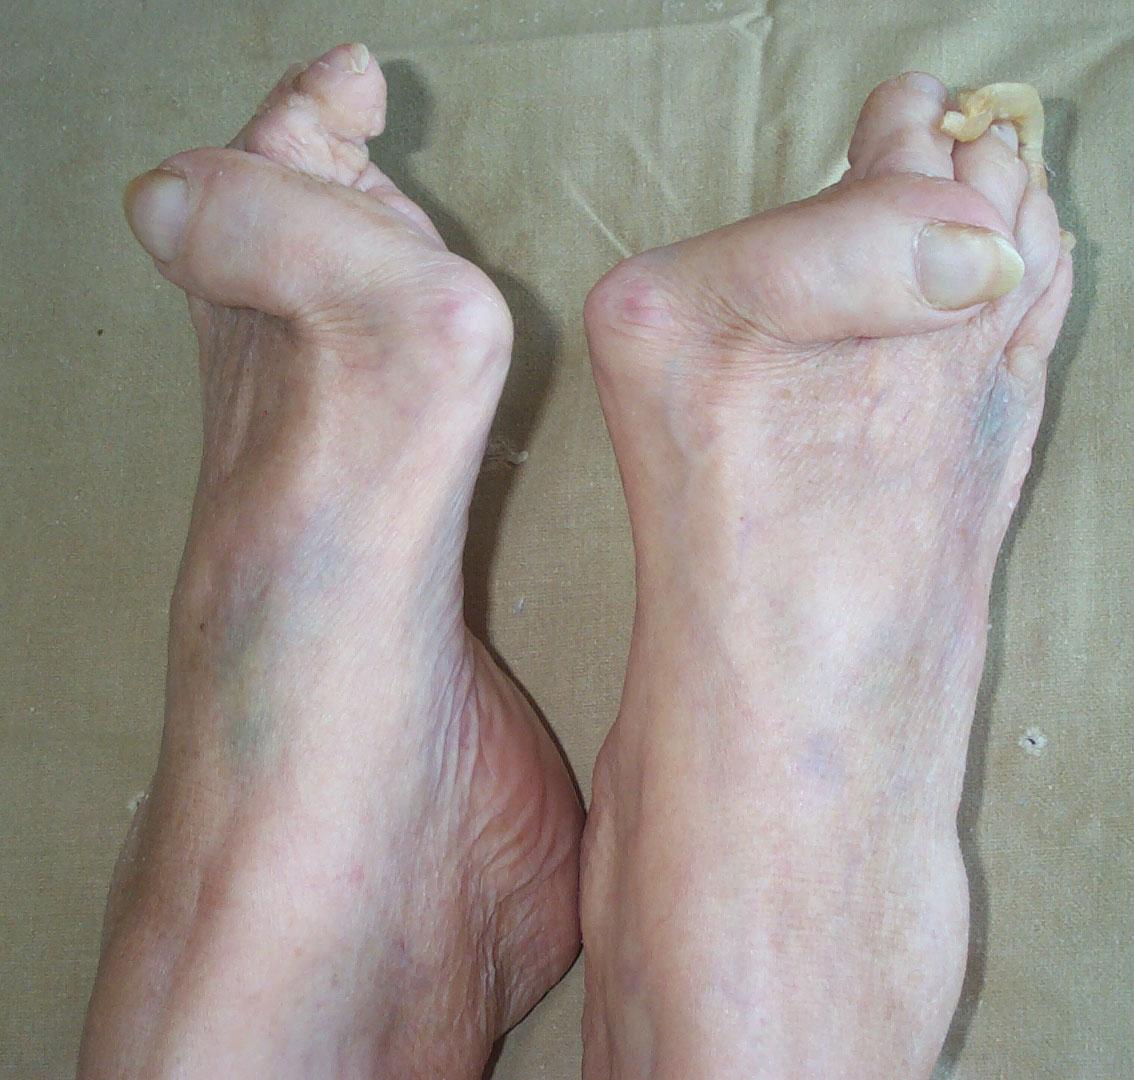

Больной С., 41 года, работает длительное время грузчиком мясокомбината. При опросе предъявляет жалобы на боли в нижних конечностях, иррадиирущие в бедра, голени, боли усиливаются во второй половине дня, к вечеру отмечается умеренная отечность мягких тканей тыла стопы. При осмотре: выраженные отклонения первых пальцев обеих стоп кнаружи, боли при ходьбе и в положении стоя, припухлость передних отделов стоп, на подошвенной поверхности стоп – натоптыши. Имеются сгибательные и разгибательные контрактуры суставов пальцев. Носит широкую обувь, на 1-2 размера больше обычной, боли усиливаются к смене погоды, сезона, смене обуви, при прыжках и беге. Иннервация и кровоснабжение конечностей не нарушены.